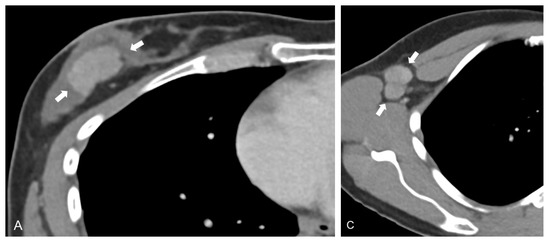

While CT-derived radiomic signatures have been evaluated in other body regions to predict distant metastases, e.g., in lung adenocarcinoma by Coroller et al. [21], they have not been used in breast cancer for this particular purpose, but instead, for prediction of treatment response [22]. Despite their selective quantification and visualization of tumor blood supply, data is particularly scarce on the significance of DECT iodine map radiomic features in oncologic imaging. In one of the few available studies, Zhou et al. demonstrated excellent performance of iodine map radiomic combined with CT imaging features in diagnosing cervical lymph node metastases of thyroid cancer, yielding an AUC of 0.895 in the validation dataset [23]. While their model was based on lymph node feature extraction, we stratified patients into metastatic and non-metastatic groups based on features of the treatment-naïve primary breast tumor (Figure 2).

Figure 2.

Axial contrast-enhanced dual-energy CT (DECT) scan of a 40-year-old patient with grade 2 luminal B invasive ductal carcinoma in the right breast. Linearly blended M_0.6 image series show a lesion in the right breast (A), as well as enlarged, round lymph nodes in the right axilla (B). In the present study, DECT iodine map radiomic signatures derived from the primary tumor (C) yield a mean AUC of 0.82 for separation of metastatic and non-metastatic breast cancers; in addition, substantial textural differences exist between primary tumor and metastatic tissue (D).